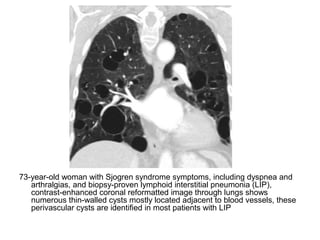

Cardiac features of pulmonary hypertension. (a) CTA shows that the right ventricular myocardium

(white arrow) is more than 4 mm thick , a finding consistent with right ventricular hypertrophy.

Straightening of the interventricular septum (black arrow) also is seen. (b) CTA shows right

ventricular dilatation which is defined as a diameter ratio (the ratio of the right ventricular diameter

[black arrow] to the left ventricular diameter [white arrow]) greater than 1:1 at the midventricular

level , Leftward bowing of the interventricular septum also is seen. (c) CTA shows reflux of

contrast material into the inferior vena cava which is dilated and hepatic veins (arrow)